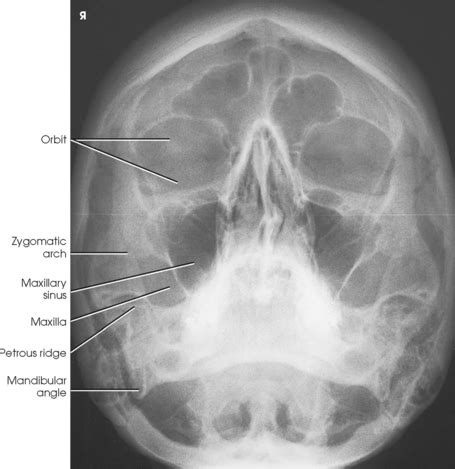

Facial Bones Radiographic Anatomy - wikiRadiography ...

Facial Bones Radiographic Anatomy - wikiRadiography ... from i.pinimg.com